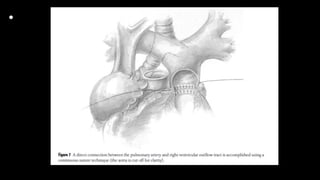

Figure 12-3

A An incision is made into the confluent

portion of the

pulmonary artery. If necessary to achieve

adequate

length, the incision is extended onto the left

pulmonary artery.

B The distal end of a prosthetic valved conduit is shortened to a point just above the heterograft valve. The

conduit shown here is meant to be generic; valves

from a variety of species have been employed. The

composite valved conduit is approximated to the pulmonary artery by continuous suture. To ensure accurate

closure, several suture loops are placed around

the apex of the incision onto the left pulmonary artery

before the prosthesis is pulled into the arteriotomy.

Generous bites of tissue are taken in each stitch,

including as much of the overlying pericardial tissue

as possible to strengthen the anastomosis and ensure

a tight tissue-to-graft approximation. The pulmonary

artery is often thin and fragile, making it extremely

important to use accurate suture technique and follow

the arc of the needle precisely. Low-flow cardiopulmonary bypass or short periods of circulatory arrest,

which reduce the amount of blood in the pulmonary

artery due to aortopulmonary collateral flow, are useful to achieve optimal visualization of the anastomosis.

The suture line is continued in a counterclockwise fashion about halfway around the anastomosis

C The suture line is completed in a clockwise fashion